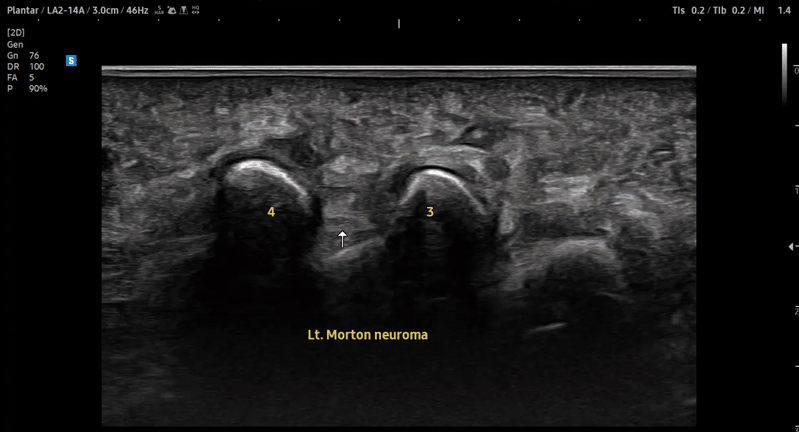

- 치료기간 : 2025. 7 . 4 ~ 2025 . 9 .1

- 치료횟수 : 10 회 (2cycle)

치료 전

치료 후